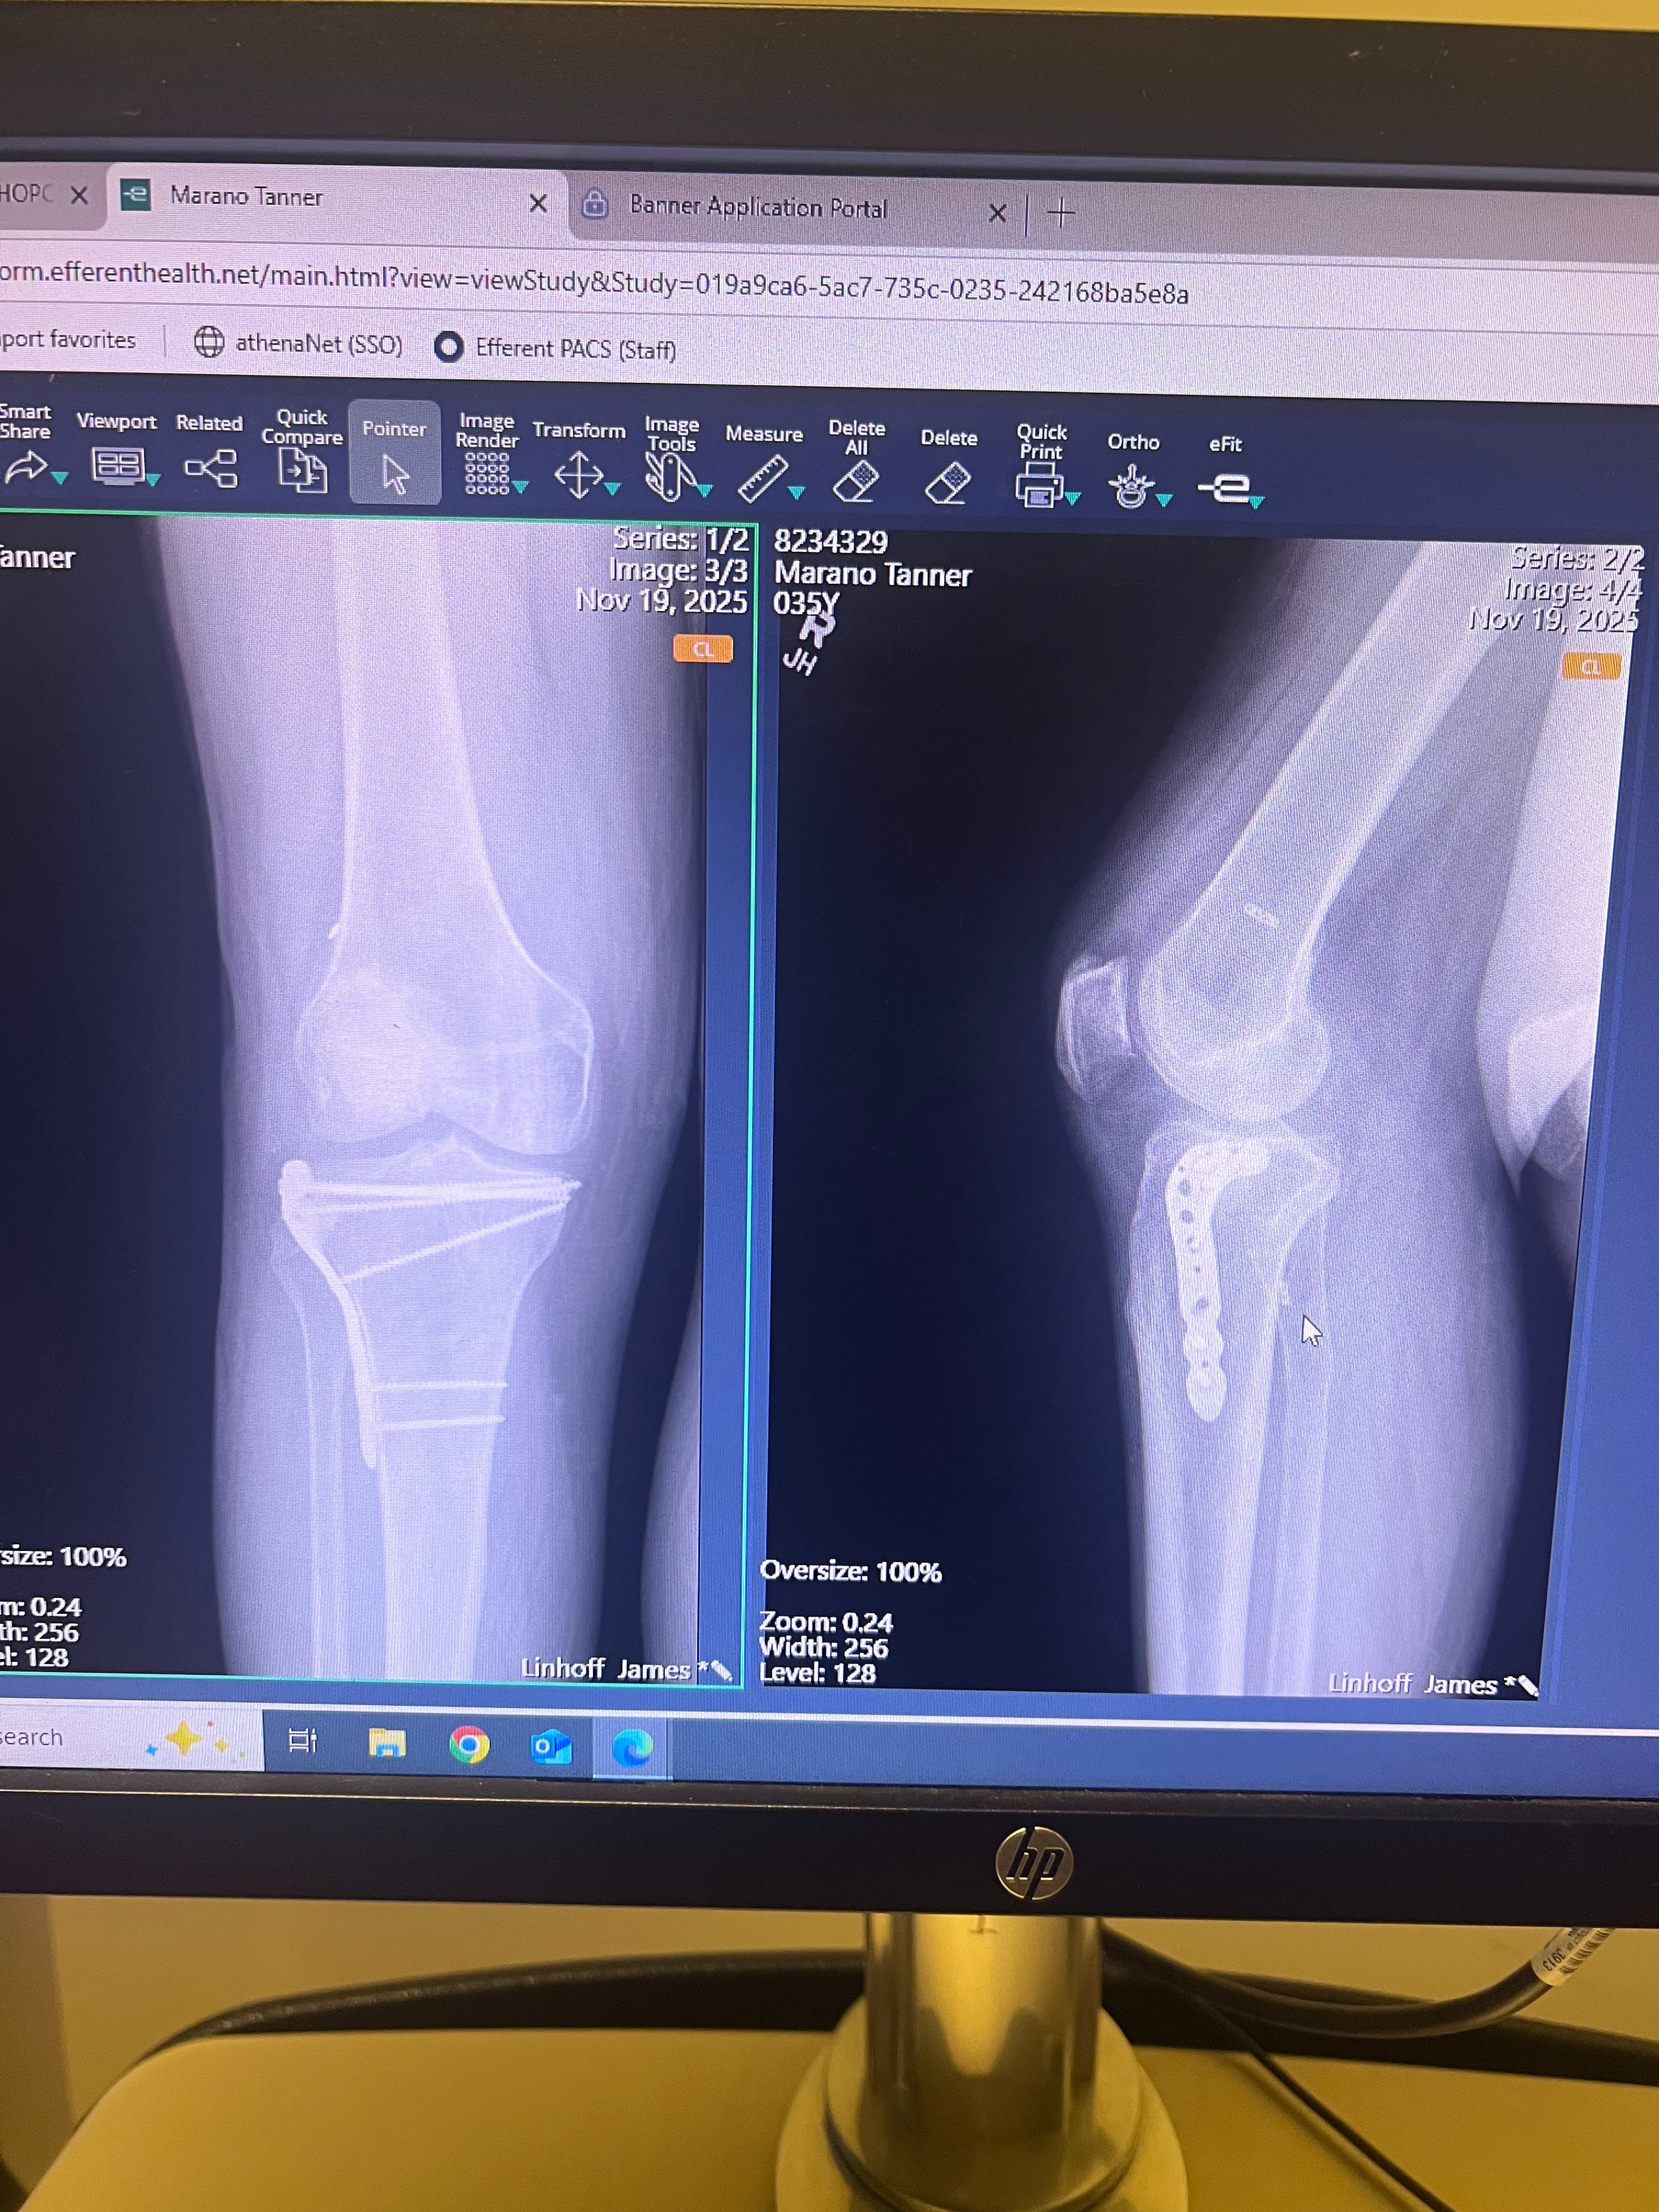

Tanner is my beloved nephew, and he truly means the world to me. He’s a devoted father and a hardworking man who always puts his young family first. Over the past year, Tanner has faced unimaginable challenges. He suffered severe injuries to his right knee, including tears to his ACL, LCL, and PCL, a fractured fibula, and a torn perineal nerve. After a long and difficult recovery, he was finally able to get back to enjoying life with his daughter. Tragically, while playing with her, Tanner fractured the tibial plate in the same knee, which required a second surgery.

Now, Tanner’s doctors have recommended stem cell therapy as the best hope for regaining mobility and improving his quality of life. Unfortunately, this treatment is not covered by his medical insurance, and the out-of-pocket costs are overwhelming. The funds raised here will go directly toward Tanner’s medical bills for stem cell therapy, giving him the chance to heal and return to the life he loves with his family.